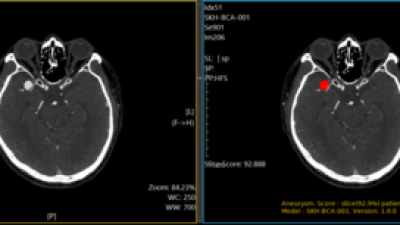

• 퍼플에이아이, 뇌동맥류 진단 AI 솔루션 식약처 의료기기 허가

기사 이미지